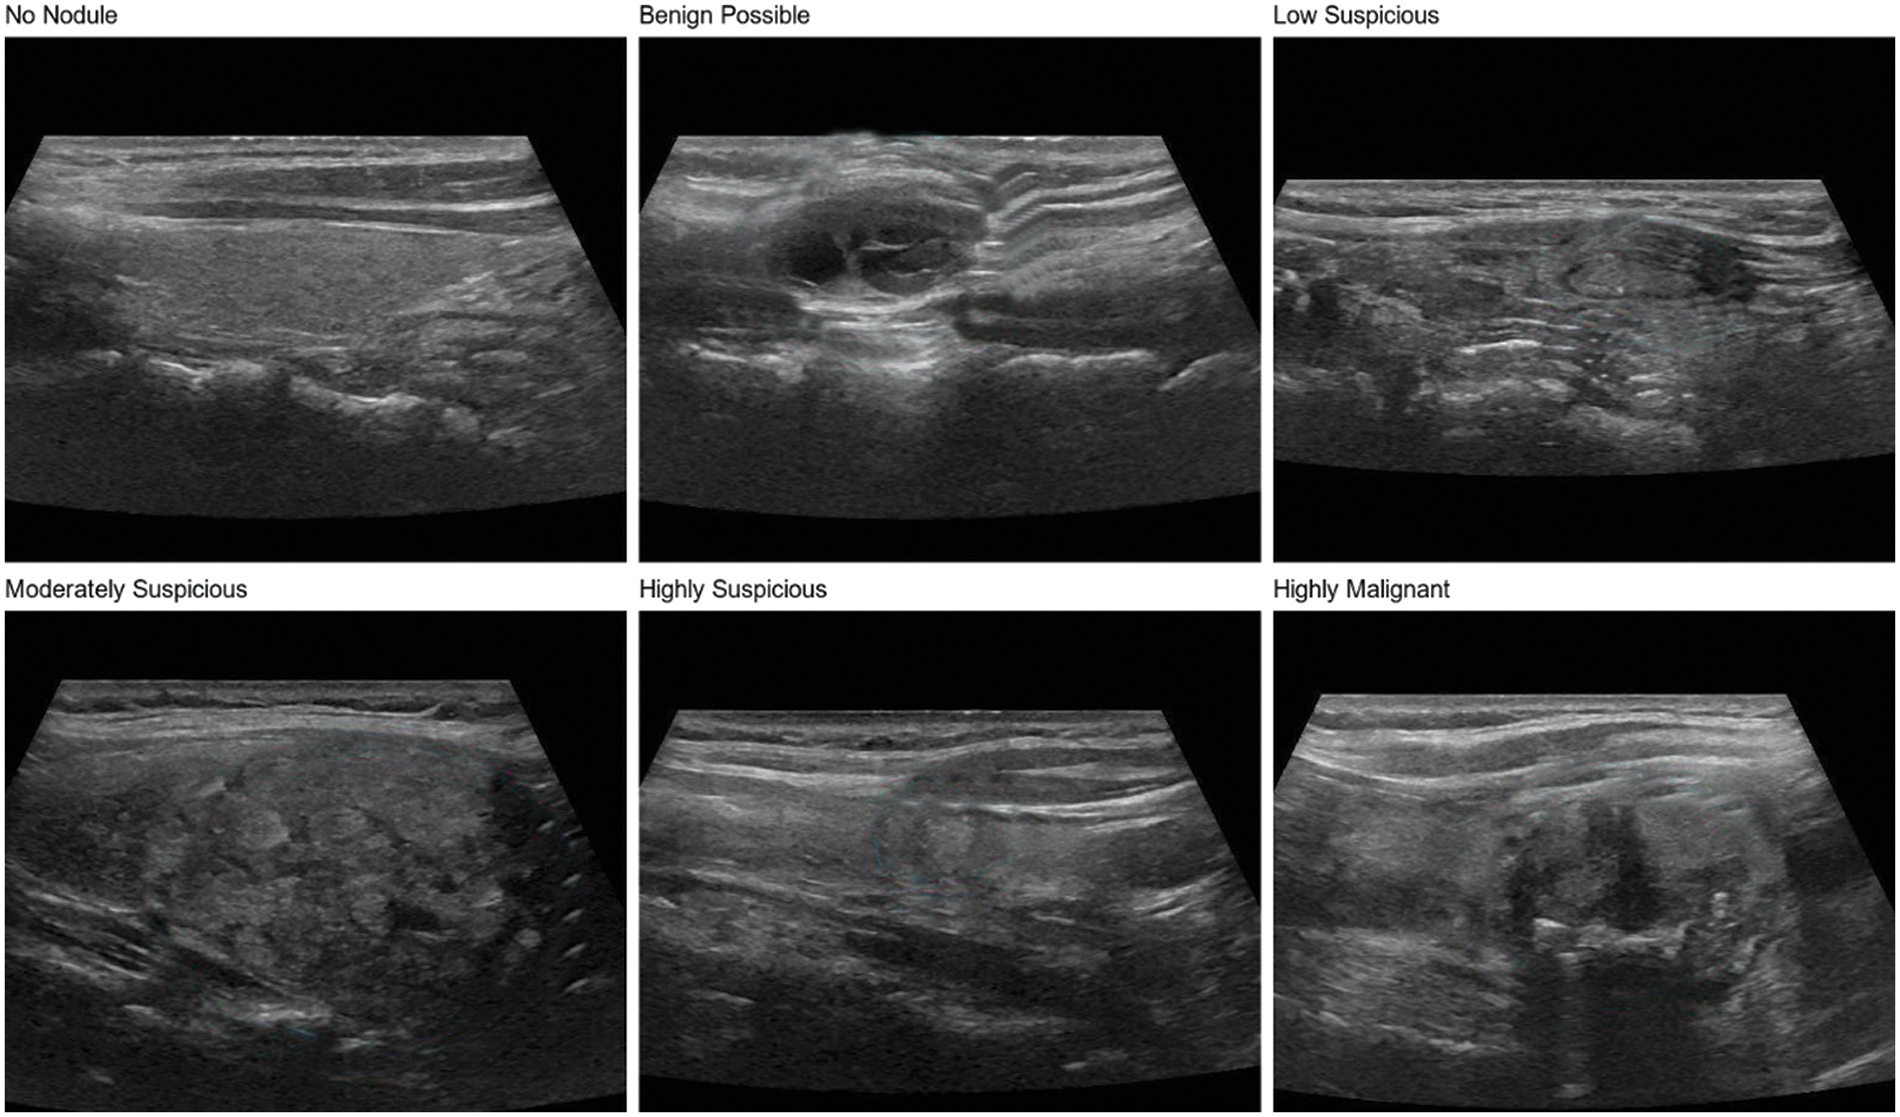

The thyroid nodule dataset used in this study is a private dataset derived from ultrasound images provided by the ultrasound department of Zhongda Hospital, affiliated with Southeast University, Nanjing, Jiangsu, China. The judgment of patient images is done by professional radiologists. The dataset contains 600 thyroid nodule images, covering six categories of a thyroid nodule, including no nodule, benign possible, low suspicious, moderately suspicious, highly suspicious, and highly malignant, as shown in Fig. 1, with 100 images for each type of nodule. In addition, the dataset includes nodules of different shapes, sizes, and densities, which is conducive to training models with a strong generalization ability to meet the needs of practical clinical applications in the hospital.

Figure 1: Six types of thyroid nodules in the dataset